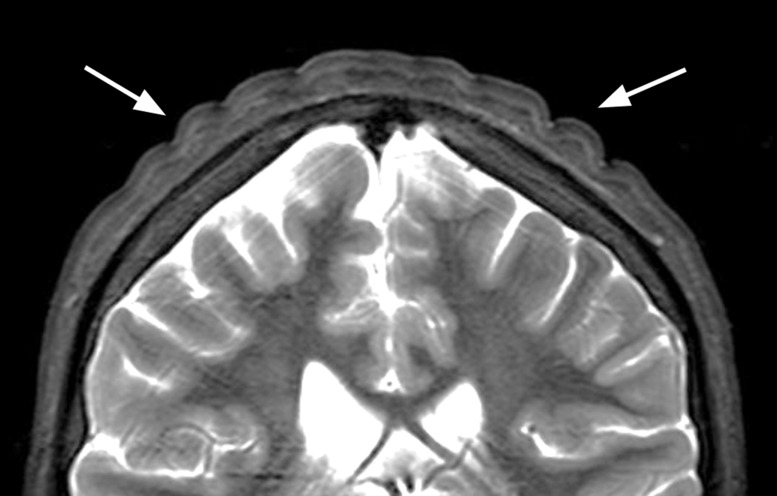

Cutis Verticis Gyrata: A Secondary Form of a Rare Skin Condition Caused by Growth Hormone Therapy.

Teaching point: To recognize cutis verticis gyrata on MRI and raise awareness of growth hormone therapy as a possible cause.